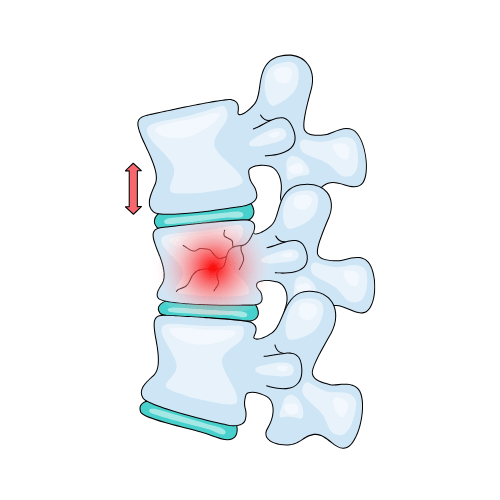

Spine surgery